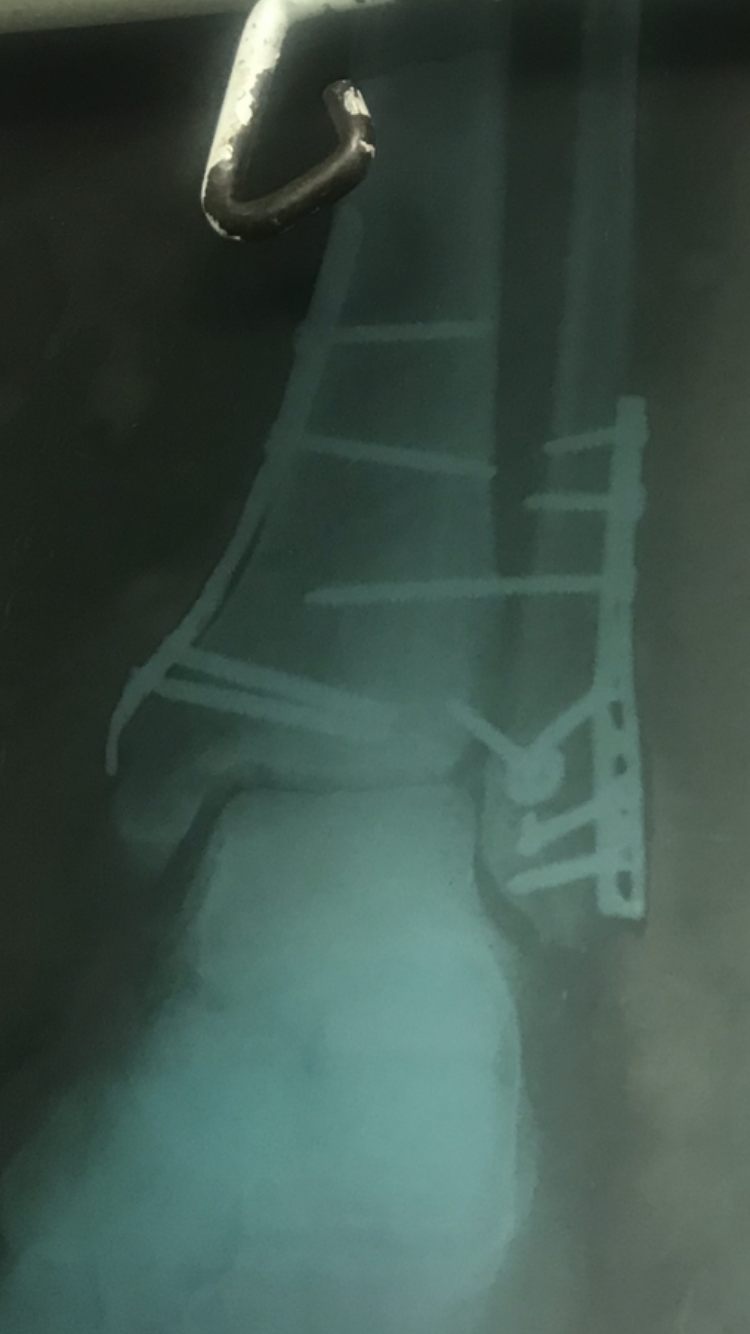

Вместо 1000 слов )

Перелом лодыжки в 3 местах

Смещение и обрыв связок

Шуруп в руке, позавчера выкрутили

На рентгене это самый длинный